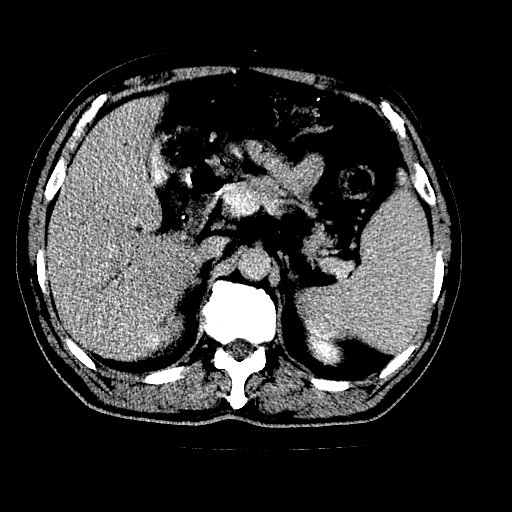

男,66岁,上腹部不适、黄染一周。彩超示:肝左叶占位,肝内胆管扩张,胆总管扩张,胆总管占位?

象胆管细胞癌,但又没有看见明显强化结节,陶瓷胆囊,十二指肠及胆总管显示不清晰,难下定论。

肝左叶不规则软组织肿块影,边缘不规整邻近肝实质受累分界不清;肝内胆管(左叶)明显扩张成“软藤状”,诊断:肝左叶胆管细胞癌。

胆囊缩小,其内胆汁浓缩,也提示梗阻部位应该位于胆囊管起始部以上或是胆囊管受累及,支持肝外胆管癌。